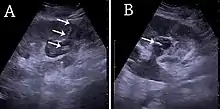

Figure 29. (A) Percutaneous nephrostomy tube placed through a calyx in the lower pole of a kidney with hydronephrosis. (B) The pigtail catheter is placed in the dilated calyx. The tube in (A) and the pigtail in (B) are marked with white arrows.[1]

Sonography is the modality of choice for guidance when performing intervention in the kidney, whether it is kidney biopsy, percutaneous nephrostomy or abscess drainage. Historically, thermal ablation of renal tumors is performed under CT guidance, as the risk of injuring neighboring intestines during the US-guided procedure was considered too high due to poor identification of the moving bowels. However, recent guidelines for renal interventional US include radiofrequency, microwave and cryoablation with US as the ideal imaging guide.[1]

For percutaneous nephrostomy and abscess drainage, either the one-step or the Seldinger technique is used. Using the Seldinger technique, the cavity is punctured with a sharp hollow needle, called a trocar. A round-tipped guidewire is then advanced through the lumen of the trocar, and after withdrawal of the trocar, a catheter or nephrostomy can be inserted over the guidewire to ensure correct placement. The one-step technique is when insertion of the drain or nephrostomy is done without the aid of a guidewire. The interventions are performed under local anesthesia and in a sterile setup. The procedures can be carried out with or without needle guidance according to preference, experience and setup (Figure 29).[1]